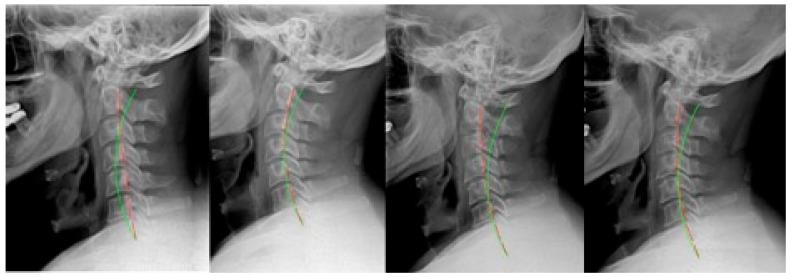

This series illustrates how rear-end impact motor vehicle collisions (MVCs) alter the cervical spine's alignment and demonstrates therapeutic use of cervical extension traction to improve lordotic alignment and other outcomes. This is a retrospective reporting of 7 adult patients (4 males and 3 females, 28-42 years) treated for cervical hypolordosis. These subjects received Chiropractic BioPhysics (CBP) rehabilitation and then were involved in a rear-end MVC. All cases had radiographic assessment that quantified the buckling of the cervical spine, presumably resulting directly from the CAD trauma. After an average of 3 years and 9 months (range: 1-7.6 years) following their initial program of care, the 7 patients sought care for a second time after the MVC. At this time, compared with their previously recorded post-treatment spine radiographs, there was an average 18.7° (range: 7.6-35.4°) reduction in cervical lordosis, a 9.2 mm (range: 3.6-19.8 mm) increase in anterior head translation (AHT), an 11.3° (range: 0.2-19.9°) decrease in the atlas plane line (APL), as well as a 35.7% (range: 22-52%) average neck disability index score (NDI) measured after the MVC. After the crash, a second round of CBP rehabilitation was administered, resulting in an average 15.1° improvement in cervical lordosis, 10.9 mm reduction in AHT, 10.4° increase in APL, and a 23.7% drop in NDI after an average of 35 treatments over 9 weeks. Treatment was universally successful, as an average 80% re-establishment of the lordosis toward its pre-injury state was found. There were no adverse events reported. This case series demonstrates that motor vehicle collisions may alter the alignment of the cervical spine. Rehabilitation of the cervical curve using extension traction improved the patients' initial pre-crash alignments toward their pre-injury alignments and was likely responsible for improvement in the patients' conditions. Clinical trials are needed to confirm these findings.

本系列阐述了机动车追尾碰撞(MVCs)如何改变颈椎排列,并展示了颈椎伸展牵引在改善前凸排列及其他结果方面的治疗用途。这是一项对7例因颈椎前凸不足接受治疗的成年患者(4例男性和3例女性,年龄28 - 42岁)的回顾性报告。这些受试者接受了脊椎矫正生物物理学(CBP)康复治疗,随后遭遇了机动车追尾碰撞。所有病例均进行了影像学评估,量化了颈椎的屈曲情况,推测这是由追尾创伤直接导致的。在其初始治疗方案实施平均3年9个月(范围:1 - 7.6年)后,这7例患者在追尾碰撞后再次寻求治疗。此时,与之前记录的治疗后脊柱X光片相比,颈椎前凸平均减少了18.7°(范围:7.6 - 35.4°),头部向前平移(AHT)增加了9.2毫米(范围:3.6 - 19.8毫米),寰椎平面线(APL)减少了11.3°(范围:0.2 - 19.9°),并且追尾碰撞后测量的颈部残疾指数(NDI)平均得分增加了35.7%(范围:22 - 52%)。碰撞后,进行了第二轮CBP康复治疗,在9周内平均进行35次治疗后,颈椎前凸平均改善了15.1°,AHT减少了10.9毫米,APL增加了10.4°,NDI下降了23.7%。治疗普遍成功,因为发现前凸平均恢复到损伤前状态的80%。未报告不良事件。该病例系列表明机动车碰撞可能会改变颈椎排列。使用伸展牵引对颈椎曲度进行康复治疗,使患者从碰撞后的初始排列改善至损伤前的排列,这可能是患者病情改善的原因。需要进行临床试验来证实这些发现。